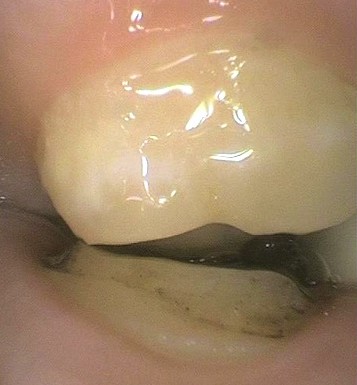

I’m currently treating a patient who came in complaining of TMD symptoms. The indications became progressively worse after some recent crowns she had done in another office. During splint therapy, one of her crowns came off; clearly the tooth had been reduced. The preparation was in contact with the opposing tooth. So what happened?